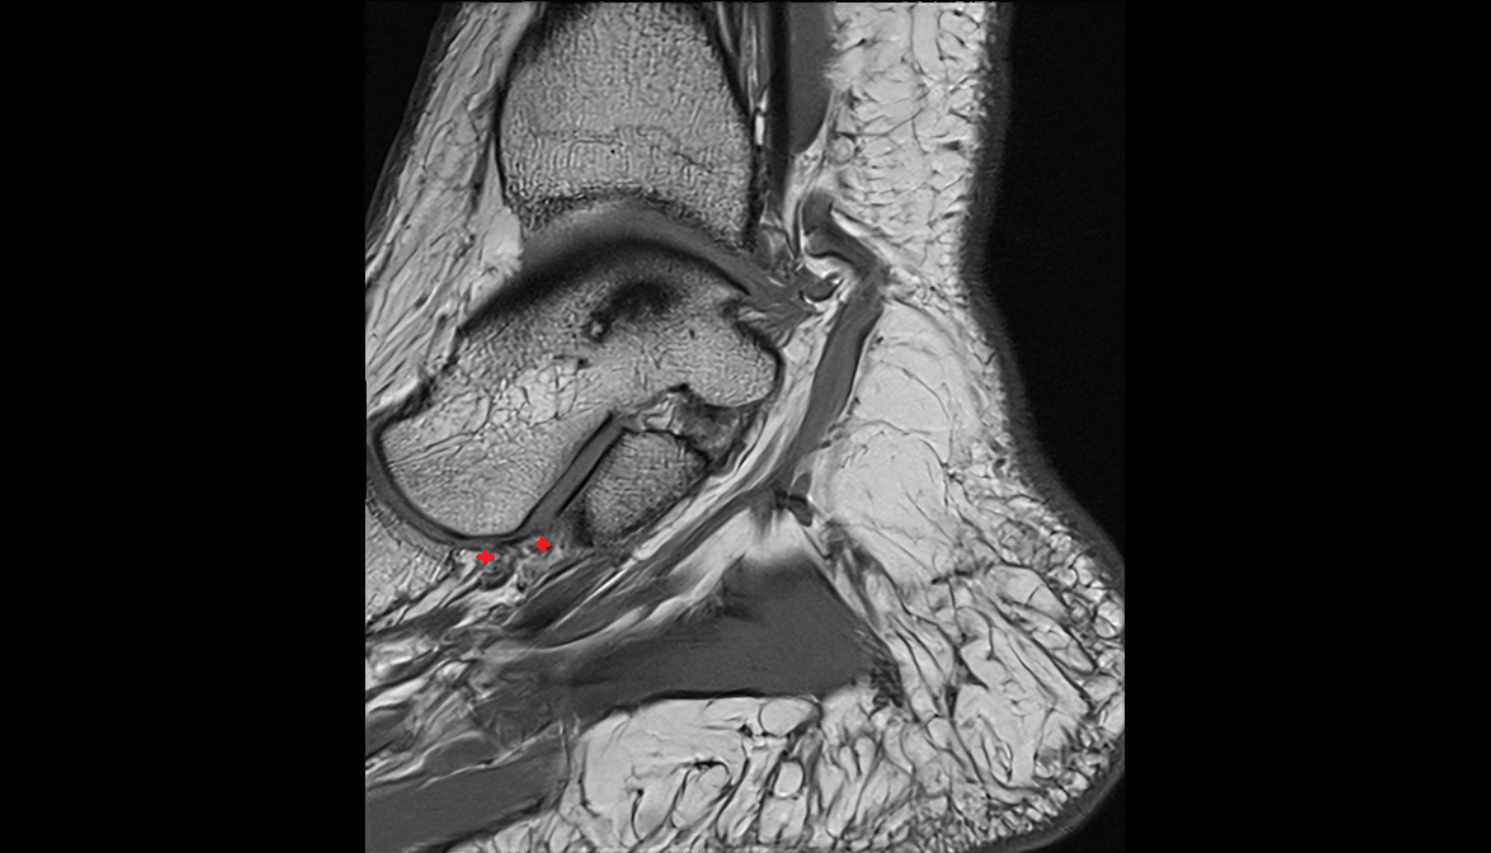

- Ankle joint

- Talus

- Calcaneus

- Anterior talofibular ligament

- Posterior talofibular ligament

- Deltoid ligament complex

- Calcaneofibular ligament